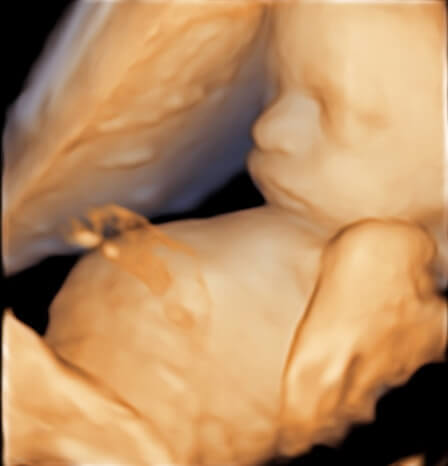

3D Ultrasound Image Gallery

3D Ultrasound Images